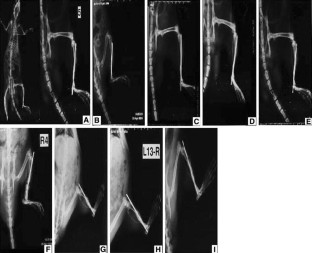

We evaluated the biological characteristics/effect of human umbilical cord-derived mesenchymal stem cells (hUC-MSCs) grafting with blood plasma on bone regeneration in rat tibia nonunion. SD rats (142) were randomly divided into four groups: fracture group (positive control); nonunion group (negative control); hUC-MSCs grafting with blood plasma group; and hUC-MSCs grafting with saline group. Rats were administered tetracycline (30 mg/kg) and calcein blue (5 mg/kg) 8 days before killing. The animals were killed under deep anesthesia at 4 and 8 weeks post fracture for radiological evaluation and histological/immunohistological studies. The hUC-MSCs grafting with blood plasma group was similar to fracture group: the fracture line blurred in 4 weeks and disappeared in 8 weeks postoperatively. Histological/immunohistological studies showed that hUC-MSCs were of low immunogenicity which merged in rat bone tissue, differentiated into osteogenic lineages, and completed the healing of nonunion. After stem cell transplantation, regardless of whether plasma or saline was used, new multi-center bone formation was observed; fracture site density was better in stem cell grafting with blood plasma group. We, therefore, concluded that the biological characteristics of hUC-MSCs-treated nonunion were different from the standard fracture healing process, and the proliferative and localization capacity of hUC-MSCs might benefit from the use of blood plasma.